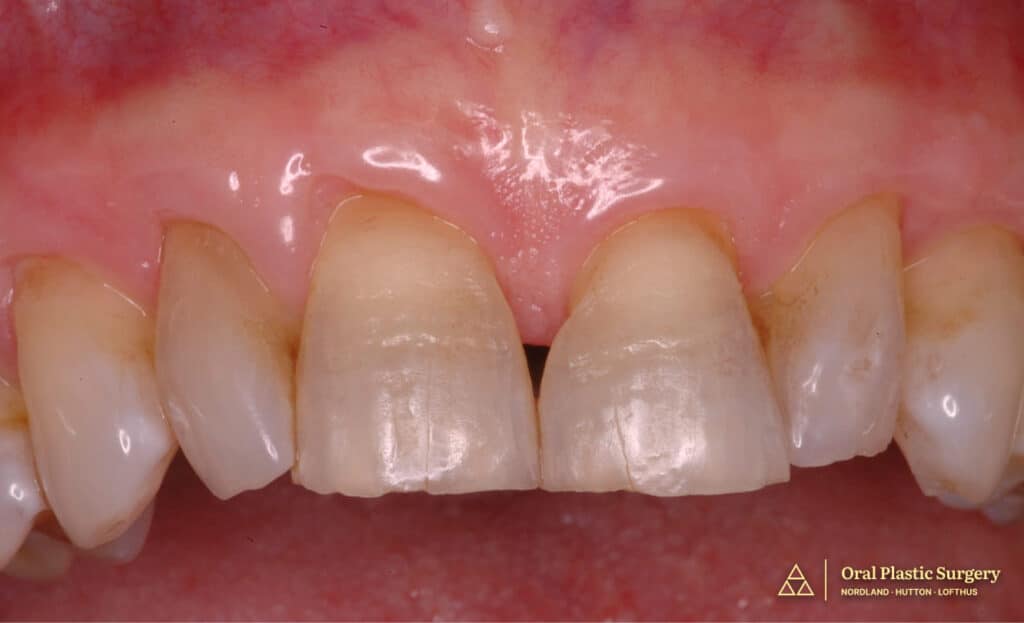

Post connective tissue grafting showing dramatic improvement in root coverage, tissue color, and gingival contour prior to final restorative work.

Case Progression & Key Milestones

Periodontal Grafting: Connective tissue grafting was performed on 16 anterior teeth (8 maxillary, 8 mandibular) to address extensive recession and create an ideal foundation.

Soft Tissue Maturation: The grafted tissue was allowed adequate time to heal, integrate, and mature before restorative work began.

Dramatic Intermediate Improvement: The gingival grafting alone resulted in a dramatic improvement in smile aesthetics by reducing root exposure and improving tissue color and contour.